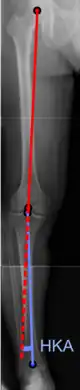

The degree of varus or valgus deformity can be quantified by the hip-knee-ankle angle,[33] which is an angle between the femoral mechanical axis and the center of the ankle joint.[34] It is normally between 1.0° and 1.5° of varus in adults.[35] Normal ranges are different in children.[36]

Hip-knee-ankle angle by age, with 95% prediction interval.[36]

Hip-knee-ankle angle by age, with 95% prediction interval.[36]